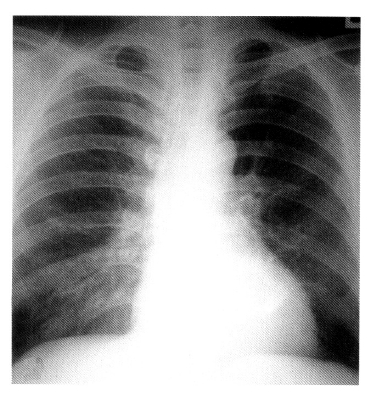

Serial chest radiography (Figure 2A, 2B) and high resolution computed tomography (Figure 3A, 3B, 3C) showed that the pulmonary nodules and patchy densities migrated to other sites and changed in shape and size daily. On the second day of admission, the patient underwent fiberoptic bronchoscopy that revealed no endobronchial lesion. The bronchoalveolar lavage (BAL) fluid had cell proportions of 45% macrophage 15% lymphocytes, 15% neutrophils, and 25% eosinophils (Figure 4). The BAL fluid was negative for bacterial, acid-fast bacilli, and fungi. A transbronchial lung biopsy was performed at the right middle lobe. Microscopy of the lung tissue showed eosinophilic infiltration (Figure 5). Abdominal ultrasound revealed no specific abnormalities except mild splenomegaly. On the ninth day of admission, migrating nodular densities on chest radiographs decreased and then disappeared dramatically following oral praziquantel therapy (Figure 6). Blood eosinophilia consequently decreased and normalized. There was no evidence of recurrence after one year of follow-up.

Figure 6.

Chest radiograph shows resolution of nodular densities after oral praziquantel therapy.